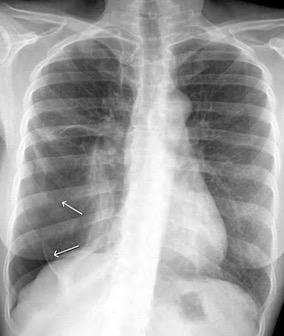

En relación con trasudados tabicados. Insuficiencia cardiaca

Hipoalbuminemia

Cirrosis / Fallo renal.

Operado aneurisma (prótesis). Líquido tabicado en cisuras

Fernandes de Paula MC et al. Focal pleural tumorlike conditions: Nodules and masses beyond mesotheliomas and metastasis. Respiratory Medicine 2015.

Derrame pleural “encapsulado”

“Tumor fantasma”

Asociado a fallo cardiaco. ( “Pleuritis adhesiva”). Buch KP. Chest. 2000